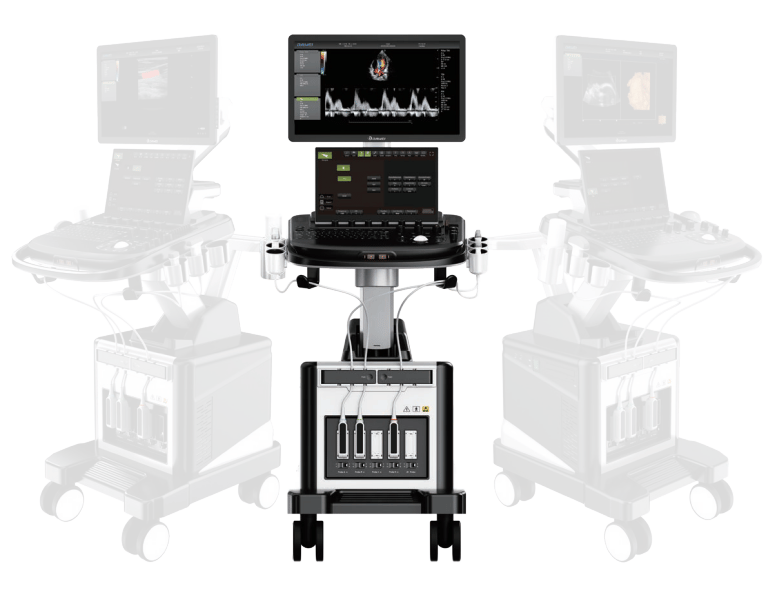

Equipment Supply

Providing top-quality medical devices to hospitals and clinics.

Our Products

A glimpse into the medical supplies we provide daily.